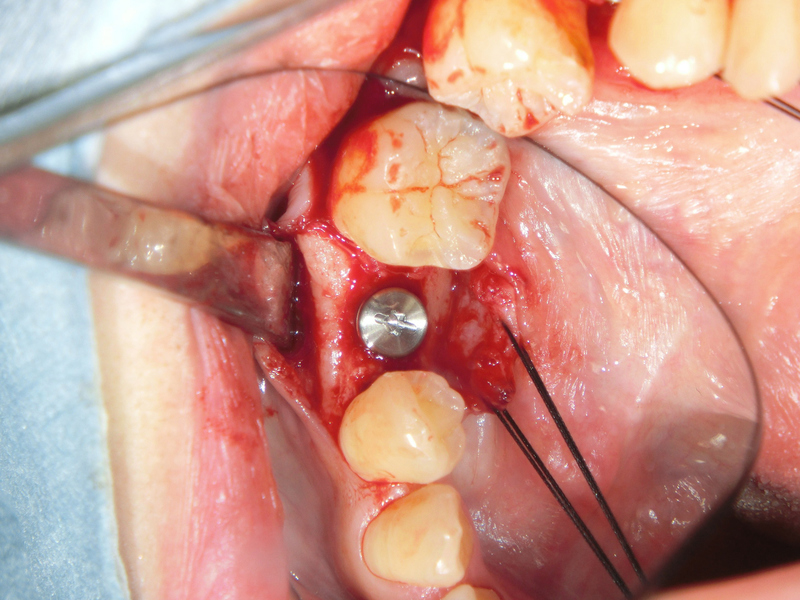

⑥二次手術(アバットメント・人工歯装着)

顎の骨とインプラントがしっかりと結合したらインプラントの上にアバットメントと言われる連結部を取り付けます。そのアバットメントの上に人工歯を装着します。